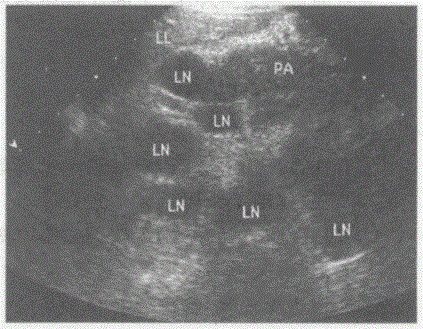

问题 临床资料:男,55岁,胃癌术后5年。 超声综合描述:脊柱前方腹主动脉周围可见多个大小不等的类圆形低回声区,最大1.8cm×1.3cm,长径/短径比值<2,边界尚清,部分融合。 超声提示:

选项 A.肠系膜癌 B.肠系膜多发囊肿 C.腹膜后多发囊肿 D.腹膜后肿大淋巴结

答案 D